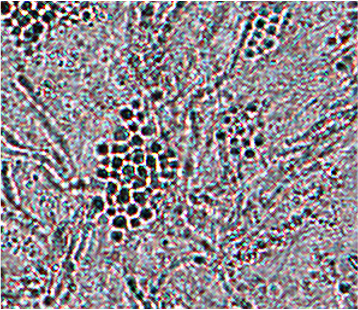

Im Tesaabrisspräparat in Methylenblaufärbung werden Hyphen und Sporenhaufen sichtbar (sogenannter Aspekt der "Spaghetti und Fleischbällchen") (Abb. 7,8).